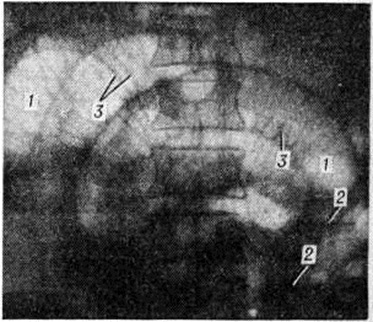

При парезе кишечника, протекающем с нарушением моторной функции, но без нарушения переваривания и всасывания, выявляется очаговый отёк цитоплазмы и набухание матрикса митохондрий каёмчатых энтероцитов при сохранении чётких структур микроворсинок щёточной каймы, элементов пластинчатой сети. В собственном слое кишечной ворсины наблюдаются признаки отёка, полнокровие капилляров, лимфостаз. В поздней фазе динамической Непроходимость кишечника отмечается укорочение и уплощение каёмчатых энтероцитов, снижение активности кислой и щелочной фосфатаз в щёточной кайме. При электронной микроскопии выявляется очаговое расплавление микроворсинок с формированием крупных вакуолей апикальной цитоплазмы и отрывом клеточных фрагментов в просвет кишки. Блок всасывания проявляется выраженным отёком клеток, сужением межклеточных щелей и нарушениями в строении щёточной каймы: характерны укорочение, фрагментация микроворсинок, разрыхление терминальной сети, дистрофические и некробиотические изменения каёмчатых энтероцитов, что свидетельствует о нарушении пристеночного пищеварения и ферментативного гидролиза. В капиллярах стромы кишечных ворсин отмечаются полнокровие, агрегация эритроцитов, периваскулярные кровоизлияния, микротромбозы (рисунок 4). После ликвидации динамической Непроходимость кишечника, то есть при восстановлении секреции, переваривания и всасывания, морфологически отмечается нормализация структур щёточной каймы, митохондрий, появляются признаки гиперплазии элементов гладкой и гранулярной эндоплазматической сети каёмчатых энтероцитов при сохранении очагового отёка базальных отделов цитоплазмы. Узлообразование кишок возникает между петлями двух отделов кишечника, чаще между тонкой и толстой (преимущественно сигмовидной ободочной) кишкой. Петля кишки с длинной брыжейкой перекидывается через петлю другой, ущемляя её, при этом возникает расстройство кровообращения с рано развивающейся гангреной кишки. Заворот кишок характеризуется перекручиванием, поворотом брыжейки и петель вокруг продольной оси магистральных брыжеечных сосудов на 180—360—720°. При этом в первую очередь происходит тромбоз сосудов, вследствие чего в перекрученном участке кишки нарушается кровообращение. Странгуляционные борозды в стенках кишок не формируются, но в ткани брыжейки видна полоса ущемления в виде зоны кровоизлияний, выраженность которой зависит от обилия жировой клетчатки. Расслаивающие кровоизлияния в стенке кишки сочетаются с ранним тромбозом вен и артерий во всех слоях и бурной воспалительной реакцией, достигающей характера флегмоны. Нервные стволы брыжейки и ганглии солнечного сплетения быстро разрушаются вплоть до распада нейронов (рисунок 5). Инвагинация кишок вызывается нарушением и дискоординацией её моторной функции. Спастически сокращённый участок втягивается в отдел, имеющий обычный просвет. Способствующим моментом может стать воспалительный процесс в стенке кишки, опухоль, инородное тело, клубок аскарид. Внедряющийся участок втягивается вместе с брыжейкой, создавая внутренний цилиндр инвагината. Серия стойких спазмов может вызвать двойную, тройную инвагинацию. Наиболее глубоко внедрившуюся часть кишки называют головкой инвагината. Она нередко оказывается плотно вколоченной, в ней развивается резкий отёк, стаз, а в дальнейшем некроз. Ввиду того что головка инвагината изолирована от брюшной полости, перитонит развивается позднее, чем при других формах Непроходимость кишечника Наружный цилиндр инвагината оказывается резко напряжённым, бледно-синюшным, но сохраняет структуру слоёв до двух и даже более суток, поскольку брыжейка этого отдела не ущемлена. Обтурационная Непроходимость кишечника характеризуется изменением приводящего отдела кишки, который переполняется содержимым и после периода усиленной перистальтики паретически расширяется. Расстройства микроциркуляции в его стенке и деструктивные изменения нарастают постепенно. А. С. Альтшуль обнаружил в эксперименте дистрофические и атрофические изменения интрамуральных нервных ганглиев, что можно считать причиной необратимых расстройств моторной функции приводящего отдела.

Динамическая непроходимость на почве тромбоза или эмболии завершается развитием геморрагического или смешанного инфаркта с последующим некрозом кишки и перитонитом (смотри полный свод знаний Кишечник, Перитонит). Обратимость процессов в кишечной стенке и брыжейке определяет жизнеспособность кишки в послеоперационном периоде и, следовательно, исход заболевания. В момент устранения непроходимости без резекции кишки (деторсия, рассечение спаек, дезинвагинация и тому подобное) расстройства микроциркуляции возрастают в ущемлённом отделе или в зоне бывшего заворота. В зависимости от выраженности этих расстройств требуется различное время для восстановления морфофункциональных свойств кишки. По данным ряда исследователей, при странгуляционных формах Непроходимость кишечника возможность регенерации зависит от сроков, прошедших от момента прекращения кровообращения в стенке кишки. При длительности его в пределах 6 часов на восстановление слизистой оболочки требуется от 12 до 30 дней. Вначале начинается регенерация эпителия крипт под слоем некроза (цветной рисунок 2) при сохранении активности неспецифической щелочной фосфомоноэстеразы в базальной мембране (цветной рисунок 3). Затем восстанавливается эпителиальный покров ворсин (цветной рисунок 5) и возобновляется периодическая секреция плотной части кишечного сока (цветной рисунок 4). Наблюдается энергичное деление энтероцитов. В мышечном слое на периферии расслаивающих кровоизлияний через сутки после устранения непроходимости (цветной рисунок 6) наблюдается дегрануляция тучных клеток, становится резкоположительной реакция эритроцитов на сульфгидрильные группы, разрушающиеся волокна становятся ШИК-положительными. Через месяц на фоне свежего рубца выявляется диастаз мышечных элементов без восстановления мышечных контактов. Возможность регенераторного процесса, протекающего на фоне отёка и кровоизлияний (рисунок 6), в первую очередь зависит от сохранения нервных рецепторов и волокон мышечного слоя. Внекишечные изменения при Непроходимость кишечника неспецифичны и отражают явления токсического шока, расстройств обмена и перитонита. Дистрофические процессы в миокарде, печени, почках на фоне острых гемодинамических нарушений могут завершиться некробиозом клеток. Расстройства микроциркуляции с признаками стаза, плазморрагии, тромбоза часто возникают в сосудах головного мозга, надпочечников. Характерно, что при Непроходимость кишечника перитонит развивается на фоне стойкого пареза кишечника. Экссудат, вначале геморрагический, переходит далее в фибринозно-гнойный и гнилостный. В послеоперационном периоде нередко развивается обширный спаечный процесс. Клиническая картина и течениеДля Непроходимость кишечника характерен ряд симптомов, изменяющихся в зависимости от формы, клинические, течения и уровня непроходимости. Боль является наиболее ранним и постоянным признаком. Она обычно начинается внезапно, часто без всякой видимой причины, в любое время суток, без предвестников. Реже боль начинается постепенно и только спустя некоторое время становится интенсивной. Боль носит схваткообразный характер и постепенно нарастает. При странгуляционной непроходимости, когда ущемляется кишка вместе с брыжейкой и проходящими в ней сосудами и нервами, боль не имеет определённой локализации, вне схваткообразного приступа прекращается не полностью, а при обтурационной Непроходимость кишечника почти полностью стихает. В дальнейшем схваткообразная боль прекращается, становится постоянной, что является результатом пареза кишечника выше препятствия. Утихает она на 2—3-и сутки заболевания, когда истощается перистальтика кишечника. Исчезновение боли в этой стадии заболевания является плохим прогностическим признаком. Рвота не является постоянным признаком Непроходимость кишечника, частота её зависит от уровня препятствия в кишке, вида и формы непроходимости. При высокой непроходимости рвота может быть многократной, при этом в промежутках наблюдаются тошнота, отрыжка, икота, при низкой локализации — однократной. Когда к непроходимости присоединяется перитонит, рвота становится почти непрерывной и не вызывает чувства облегчения. При далеко зашедших формах Непроходимость кишечника у больных возникает так называемый каловая рвота вследствие гнилостного разложения содержимого приводящего отдела кишки. Вздутие живота частый симптом Непроходимость кишечника Заворот и узлообразование обычно сопровождаются неравномерным вздутием. Так, при завороте тонкой кишки появляется несколько поперечно расположенных валов в средней части живота. Видимая на глаз перистальтика типична при обтурационной Непроходимость кишечника; при непроходимости толстой кишки и нижних отделов тонкой отмечается выраженный метеоризм, чего обычно не бывает при высокой тонкокишечной непроходимости. Для динамической Непроходимость кишечника характерно равномерное вздутие живота и отсутствие видимой на глаз перистальтики. Важным симптомом Непроходимость кишечника является задержка газов и стула. Однако в первые часы после начала заболевания стул бывает самостоятельный или после клизмы, частично отходят газы, что объясняется неполным закрытием кишки или отхождением содержимого, находящегося ниже места препятствия. Каловые массы в таких случаях отходят малыми порциями, стул не облегчает страданий. Изменения со стороны языка характерны. В первые часы заболевания изменения незначительны. Однако по мере повторения рвоты и нарастания интоксикации язык становится сухим и одновременно покрывается белым или жёлтым. налётом. В терминальной стадии Непроходимость кишечника язык сухой, покрыт грязно-бурым или коричневым налётом, что свидетельствует обычно о тяжёлой интоксикации, обезвоживании и перитоните. В процессе развития заболевания значительно изменяется перистальтика кишечника. Динамика её зависит от уровня Непроходимость кишечника, а также характера течения заболевания. Так, при высокой тонкокишечной непроходимости уже в первые часы болезни перистальтика, как правило, резко усилена, иногда даже слышна на расстоянии, а при толстокишечной Непроходимость кишечника усиление перистальтики возникает гораздо позже (иногда даже на 2—3 сутки) и оно часто имеет волнообразный характер. В поздних стадиях заболевания, особенно при развитии перитонита, перистальтика постепенно ослабевает, а потом и исчезает совсем. Часто в клинические, картине Непроходимость кишечника развиваются симптомы раздражения брюшины. В начале заболевания обычно они отсутствуют. В дальнейшем выраженность перитонеальных явлений постепенно начинает нарастать, что, как правило, протекает параллельно с прогрессированием интоксикации, боли, рвоты, вздутием живота и другими симптомами Непроходимость кишечника Максимального развития симптомы раздражения брюшины достигают при перитоните, что имеет место при далеко зашедшей Непроходимость кишечника, тяжёлой интоксикации, обезвоживании и так далее Общее состояние больного особенно быстро ухудшается при странгуляционных формах, высоком уровне обтурации и при Непроходимость кишечника на почве тромбоза сосудов брыжейки. Внешний вид и положение больного зависят от формы Непроходимость кишечника и срока заболевания. Больные всегда принимают лежачее и лишь иногда коленно-локтевое положение. Выражение лица в начальном периоде характеризуется испугом, а в момент приступа боли становится страдальческим. При развитии заболевания лицо бледнеет, черты заостряются, появляется холодный пот — лицо Гиппократа (смотри полный свод знаний Гиппократа лицо). Температура тела может колебаться в широких пределах. При тяжёлых формах узлообразования и внутреннего ущемления с вовлечением в патологический процесс больших участков кишечника и брыжейки, а также при обширном тромбозе сосудов брыжейки кишечника может возникнуть коллапс и шоковое состояние со снижением температуры тела до 35°. У таких больных обычно бывает частый, порой нитевидный пульс, низкое АД. При запущенных формах непроходимости, сопровождающихся обычно прогрессирующим перитонитом, отмечается несоответствие температуры частоте пульса. Характеристика клинические, картины отдельных форм Непроходимость кишечника приведена в таблице. Течение Непроходимость кишечника зависит от многих факторов: причины и формы непроходимости, уровня препятствия (в связи с чем выделяют высокую и низкую непроходимость), возраста больного, сопутствующих заболеваний и другие Высокая Непроходимость кишечника характеризуется бурным началом заболевания, сопровождающимся ярко выраженной симптоматикой, особенно типична неоднократная рвота. Быстро нарастает интоксикация, тяжёлые нарушения водно-электролитного обмена, обезвоживание. При низкой непроходимости эти явления могут быть значительно замедлены в развитии и не столь отчётливы. Острое течение Непроходимость кишечника отличается классической клинические, картиной — наблюдаются все симптомы непроходимости. Характерной чертой острого течения является неуклонное прогрессирование заболевания, заканчивающееся, как правило, развитием перитонита, как это бывает, например, при завороте тонкой кишки или ущемлённой грыже. При подостром течении прогрессирование заболевания происходит гораздо медленнее, иногда на протяжении нескольких дней. Чаще это бывает при низкой Непроходимость кишечника обтурационного или спаечного генеза. Однако и при этом варианте течения Непроходимость кишечника, как правило, постепенно нарастают признаки прогрессирующего перитонита. Течение частичной Непроходимость кишечника имеет интермиттирующий характер: после периода полной Непроходимость кишечника пассаж по кишечнику может частично или даже полностью временно восстановиться. При этом и симптоматика Непроходимость кишечника временно ослабевает или даже исчезает совсем. Наиболее часто это встречается при различных вариантах обтурационной Непроходимость кишечника Иногда такая частичная Непроходимость кишечника может закончиться выздоровлением (например, при отхождении желчного камня или инородного тела). В большинстве случаев, однако, ремиссия в течении Непроходимость кишечника сменяется рецидивом обтурации просвета кишки с последующим развитием острой Непроходимость кишечника Клинические, картина хронический Непроходимость кишечника характеризуется периодическими запорами со вздутием кишечника и нерезко выраженным болевым синдромом (боли схваткообразные). По мере вздутия живота появляется видимая перистальтика кишечника. Клинические, картина динамической Непроходимость кишечника имеет свои особенности. Ведущими симптомами являются рвота, вздутие живота, неотхождение кала и газов. Боль и интоксикация выражены в гораздо меньшей степени, чем при механической Непроходимость кишечника, а иногда могут полностью отсутствовать. В пожилом и старческом возрасте клинические, картина Непроходимость кишечника имеет ряд особенностей. Так, при обтурационной и спаечной Непроходимость кишечника болевой синдром может быть выражен незначительно, в то время как признаки интоксикации, обезвоживания, нарушения водно-электролитного и белкового обмена весьма отчётливы. При странгуляционной Непроходимость кишечника характерно бурное течение заболевания, осложняющегося иногда уже в первые часы острыми сердечно-сосудистыми нарушениями и даже развитием шока (смотри полный свод знаний). ДиагнозДооперационный диагноз острой Непроходимость кишечника основывается на анализе анамнестических данных, выявлении характерного клинические, симптомокомплекса, а также результатах лабораторных и инструментальных методов исследования. Характерным ранним пальпаторным признаком странгуляционных форм Непроходимость кишечника служит симптом Валя (смотри полный свод знаний Валя симптом)— наличие в брюшной полости на ограниченном участке растянутой, малоболезненной петли. При лёгком толчке обычно слышен шум плеска жидкости, находящейся в переполненной тонкой кишке (симптом Склярова). При инвагинации иногда удаётся прощупать в брюшной полости плотное, болезненное образование — инвагинат. У больного при наличии клинические, картины Непроходимость кишечника необходимо тщательно обследовать брюшную стенку для выявления наружных грыж (смотри полный свод знаний Грыжи). Обязательным при Непроходимость кишечника является пальцевое исследование прямой кишки, а также вагинальное исследование, с помощью которых можно обнаружить воспалительный инфильтрат или новообразование в прямой кишке или в малом тазу, инородное тело прямой кишки, низкую обтурацию каловыми массами, а у детей иногда головку инвагината спустившегося до ампулы прямой кишки или кровянистые выделения. Характерным симптомом заворота сигмовидной кишки И. И. Греков считал «симптом Обуховской больницы» — зияние заднепроходного отверстия и расширение ампулы прямой кишки. Аускультация живота в начальных стадиях механической Непроходимость кишечника позволяет обнаружить характерные кишечные шумы, обусловленные усиленной — так называемый стенозирующей перистальтикой кишки выше места препятствия. В поздней фазе, при развитии перитонита и прогрессировании пареза кишечника, отмечается полное отсутствие кишечных шумов. Важное значение в оценке состояния больного с Непроходимость кишечника имеют данные лабораторных методов исследования. В частности при анализе крови можно обнаружить анемию (при опухолевой причине заболевания). При тяжёлых формах непроходимости, сопровождающихся обильной рвотой, нередко обнаруживаются признаки дегидратации и нарушения водно-электролитного обмена: высокие цифры Нb и гематокрита, снижение центрального венозного давления и повышение объёма циркулирующей плазмы, глобулярного объёма, объёма циркулирующего гемоглобина и объёма циркулирующего белка, гипокалиемия и гипохлоремия. Важную роль в диагностике Непроходимость кишечника играют эндоскопические методы исследования, позволяющие, в основном, уточнить характер и локализацию толстокишечной непроходимости. Так, ректороманоскопия (смотри полный свод знаний) даёт возможность диагностировать опухоли, стриктуры, инородные тела прямой, дистального отдела сигмовидной ободочной кишок. Гораздо более информативной является колоноскопия (смотри полный свод знаний), при которой удаётся осмотреть всю толстую и часть дистального отдела подвздошной кишки. При хронических, особенно рецидивирующих формах тонкокишечной непроходимости, причина её может быть установлена с помощью интестиноскопии (смотри полный свод знаний), к которой следует прибегать, когда прочие диагностические методы оказываются недостаточно информативными. В ряде случаев диагноз Непроходимость кишечника может быть поставлен при лапароскопии (смотри полный свод знаний Перитонеоскопия). Дополнительную информацию, позволяющую судить о развитии воспалительных изменений в брюшной полости, дают кристаллическая термография, тепловидение (смотри полный свод знаний Термография), локальная термометрия (смотри полный свод знаний). Рентгенологическое исследование. Методика рентгенологическое исследования при Непроходимость кишечника состоит из двух этапов. На первом этапе, кроме рентгеноскопии грудной клетки и брюшной полости, обязательно производят рентгенограммы брюшной полости в вертикальном и горизонтальном положении больного и при необходимости в латеропозиции (смотри полный свод знаний Полипозиционное исследование). В большинстве случаев первичного обзорного рентгенологическое исследования бывает достаточно для установления диагноза Непроходимость кишечника В неясных случаях для уточнения диагноза необходимо применять дополнительные методики, составляющие второй этап в диагностике. К этим методикам относятся: динамическое рентгенологическое наблюдение; контрастное исследование тонкой кишки с 50—100 миллилитров охлаждённой взвеси сульфата бария, принимаемой через рот или вводимой в двенадцатиперстную кишку через зонд; ирригоскопия. Рентгенодиагностика механической Непроходимость кишечника основывается на выявлении прямых и косвенных симптомов. При тонкокишечной непроходимости прямыми симптомами являются наличие на обзорных рентгенограммах в вертикальном положении больного тонкокишечных арок с чёткими горизонтальными уровнями жидкости и газовыми пузырями над ними — чаш Клойбера (рисунок 7), растяжение складок слизистой оболочки тонкой кишки в виде пружины (рисунок 8), переливание жидкости из одной петли в другую, выявляемое при рентгеноскопии, отсутствие газа в толстой кишке. При исследованиях в латеропозиции определяется симптом фиксации кишечных петель, то есть отсутствие смещаемости петель и арок к брюшной полости при перемещении больного из вертикального положения в латеропозицию на левом и на правом боку. При контрастном исследовании тонкой кишки выявляется её расширение выше препятствия, длительная задержка контрастного вещества в тонкой кишке с маятникообразным перемещением и остановкой его над местом непроходимости.